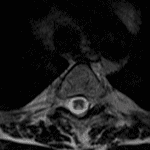

Indication: Gait imbalance, history of leukemia status post radiation therapy

- Extensive abnormal T2/STIR hyperintensity in the dorsal columns extending throughout the thoracic spinal cord without cord expansion or atrophy

- Possible additional areas of signal abnormality in the lateral columns

- Diffuse T1 hyperintense marrow signal

- Subacute combined degeneration (SCD)

Extensive abnormal T2/STIR hyperintensity in the dorsal columns and possibly also involving the lateral columns extending throughout the thoracic spinal cord, which is primarily concerning for subacute combined degeneration, though methotrexate-induced myelopathy can have a similar appearance. Recommend correlation with serum B12 values.

Diffuse T1 hyperintense marrow signal, which may represent sequela of prior radiation therapy.